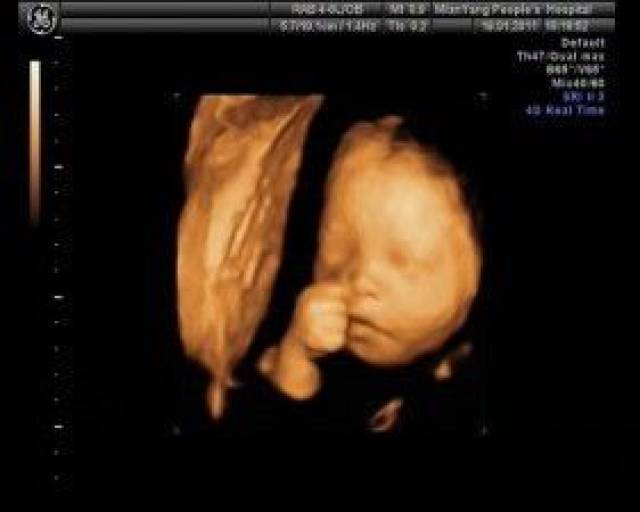

四维胎儿图片,四维图片胎儿全图

为什么胎儿的四维彩超照都那么丑有4个客观原因很难被解决

胎儿的四维彩超,和实际的样子有区别吗?戳进来,看看对比

怀孕24-28周是照四维彩超的最佳时间,因为胎儿24周左右正是大脑突飞

孕妇做四维发现胎儿在微笑,太暖心了!

四维彩超如何看胎儿性别吗